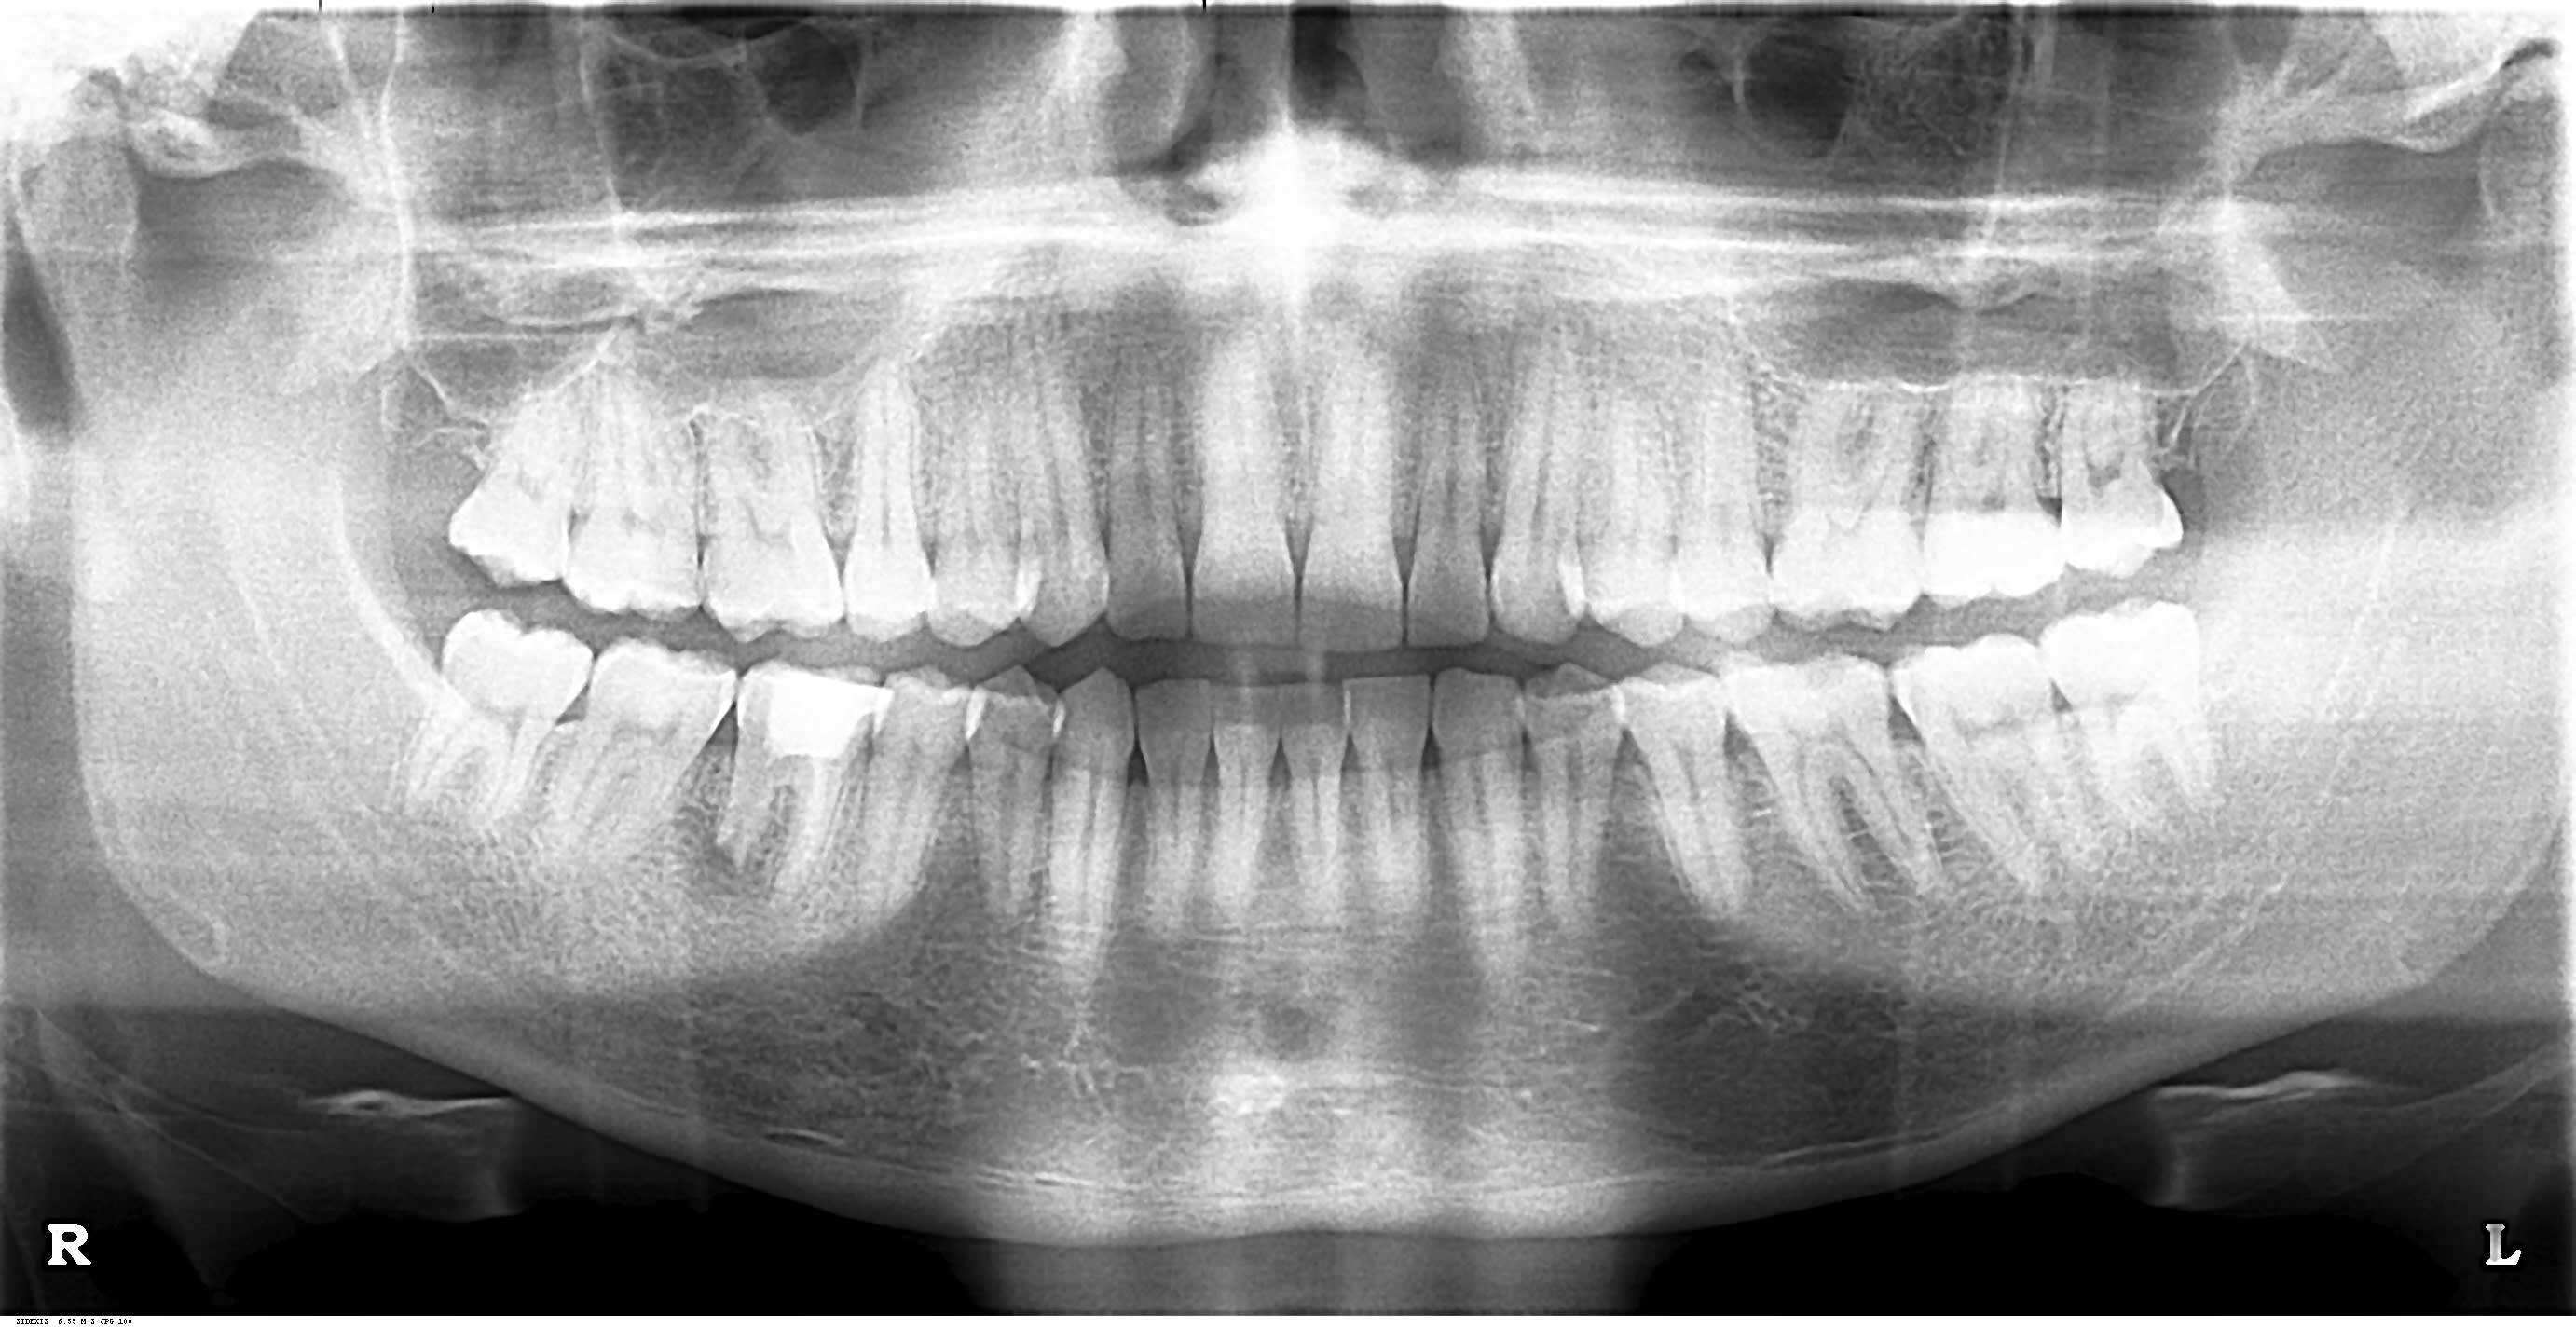

Je souhaiterais avoir vos avis concernant la prise en charge de cette dent. Une endo a été faite, mais seuls les canaux mésiaux ont été obturés.

L'apex de racine distale a été totalement grignoté par l'abcès . J'ai drainé et mis le patient sous AB.

Comment obturer la racine D? Que feriez-vous?